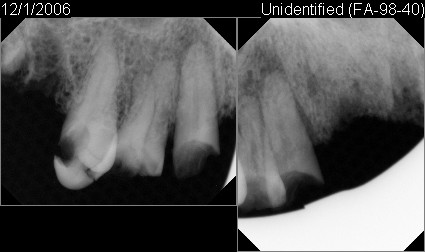

FA-1996-25